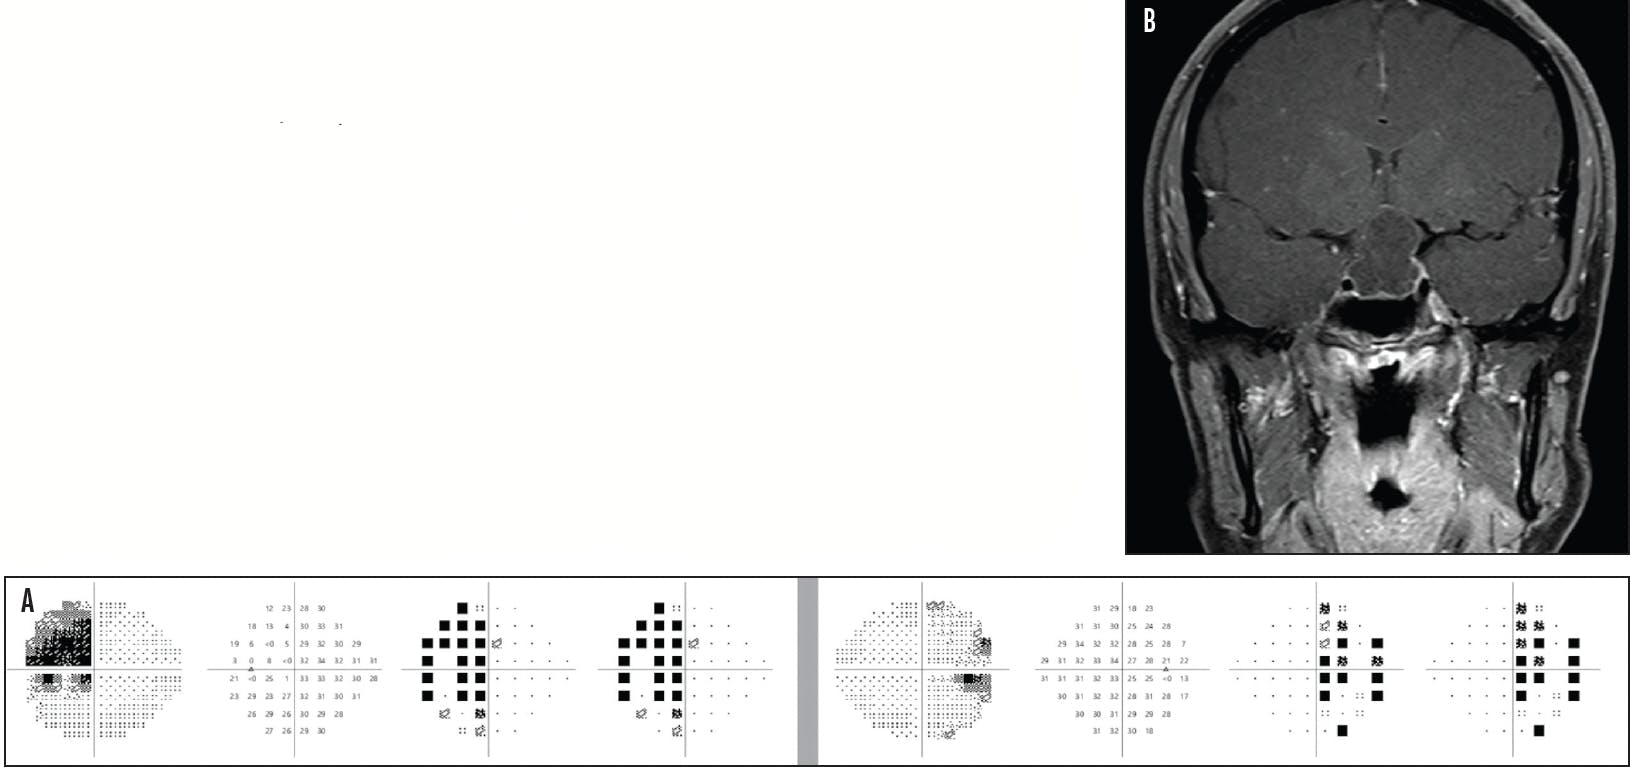

Compressive optic neuropathy typically progresses slowly and is often characterized by dyschromatopsia out of proportion to the patient’s visual acuity. In contrast, the visual acuity and color vision of patients with NTG are often preserved until late in the disease course.1 Although compressive optic neuropathy is generally expected to present more with pallor than cupping, cupping can develop in the setting of a compressive lesion, thereby complicating the diagnostic process.2 Compressive lesions can produce a variety of visual field defects, some of which may mimic glaucoma; however, visual field defects respecting the vertical meridian (eg, homonymous or bitemporal field defects) and markedly asymmetric or unilateral field defects should raise suspicion for a nonglaucomatous process (Figure 1).

Figure 1. Humphrey visual field testing (Carl Zeiss Meditec) with the 24-2 Swedish interactive thresholding algorithm–Fast (SITA-Fast) demonstrates incomplete bitemporal hemianopia (A). A T1-weighted, postcontrast coronal MRI scan shows an arachnoid cyst with compression of the optic chiasm (B).